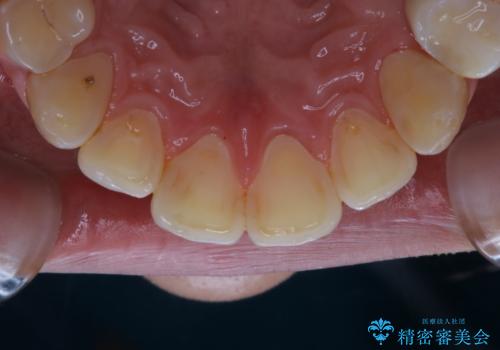

紅茶による着色を1日できれいに

- 紅茶を頻繁に飲むため、歯の黄ばみが気になるとのことでした。PMTC60分コースを行いました。

PMTC(保険外治療)は、毎日の歯磨きで落としきれない汚れや、コーヒ、紅茶・タバコのヤニなどの着色も除去します。目には見えない歯と歯の間・歯肉の境目などに残っているプラーク(歯垢)もしっかり取り除きます。PMTCでは専門的な機械や材料を使用して、徹底的に汚れを除去するため、虫歯・歯周病・口臭予防などにつながります。

また、仕上げのトリートメントでは歯の表面の凸凹にミネラルを補給して、ツルツルの表面に仕上げます。定期的にPMTCを行うことにより、歯質の強化になり着色がつきにくい状態になります。